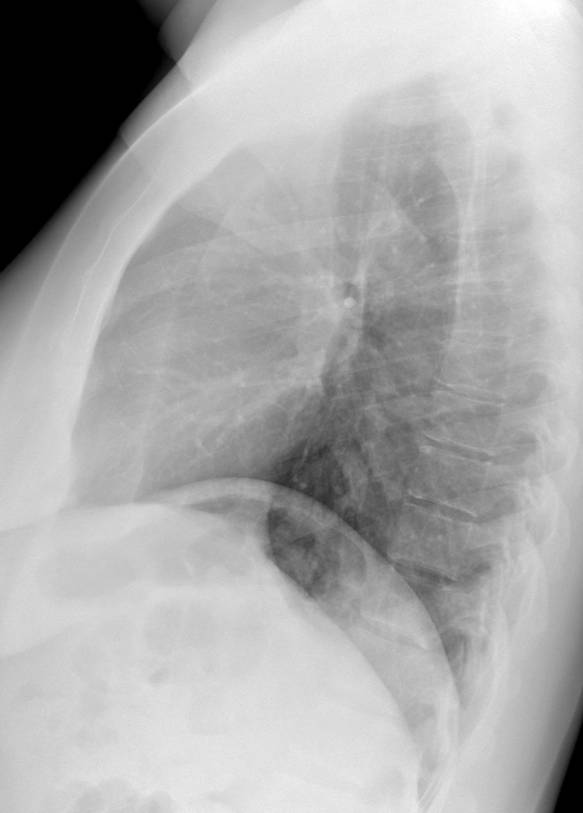

Sign? A. Hampton hump B. Hilum overlay C. Ring around the artery D. Knuckle

#radres#radedu#meded#FOAMed@TanMohammedMD@DarelHeitkamp@StefanTigges Answer: Knuckle. CXR - enlarged proximal R hilum with abrupt tapering; CT - enlarged R pulmonary artery filled with thrombus.pic.twitter.com/UJnJvi8GyZ